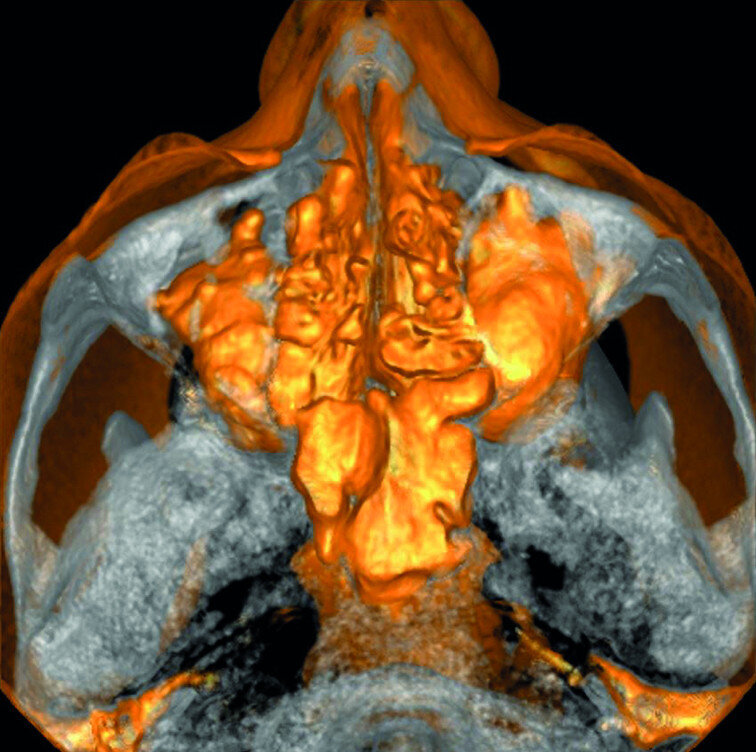

A patient was referred to the office with problems related to separated files. He was a pilot and was complaining of pus draining from his nose when flying. From the preoperative radiograph (Fig. 1), it was clear that there were two separated file fragments in the mesial canals and one cone passing beyond the apex in the palatal root. I requested an iCAT scan, and from this, the left sinus was clearly almost full with inflammatory fluid (Fig. 2) and the cone in the palatal canal was clearly emerging into the sinus. We could also see the two separated files in the two mesial canals clearly in the MPR view (Figs. 3 & 4), as well as another file entering the sinus and not attached to the canal (Fig. 5). We could see the file using different filters (Figs. 6–9), as well as the inflammation inside the sinus and the separated file. We additionally gained a better idea of the location of the cone protruding from the palatal canal into the sinus.

The maxillary sinus is located at a lower level than the floor of the nasal cavity, and it is closely associated with maxillary tooth roots. [6] Some studies have shown that the palatal root of maxillary first molar is most commonly found inside the maxillary sinus, [7] while others have found that the mesiobuccal roots of the second molars have the greatest protrusion into the sinus. [8]

Diagnosing maxillary sinusitis of dental origin requires a careful clinical and radiographic examination. It has been suggested that the incidence of sinusitis of dental origin is increasing, [9] or at least we are becoming more aware of it. One reason for this finding may be the availability of improved imaging, such as in-office CBCT scanning. [10] CBCT provides an accurate evaluation of maxillary bone quality and quantity around posterior root apices without the distortions and superimposition caused by teeth and the surrounding structures, and it can give us a clear idea about the position of the roots and apices vis-à-vis the sinus cavity and the membrane. If the Schneiderian membrane has a thickness of 0.5 mm and greater, with or without the presence of an apical radiolucency, the tooth is considered to have an endodontic infection. Sinus membrane perforations can have several sequelae, including reduced resistance to infection, and the most frequent complications are nose bleeding, sinus obstruction, and acute or chronic sinus infection. [13]